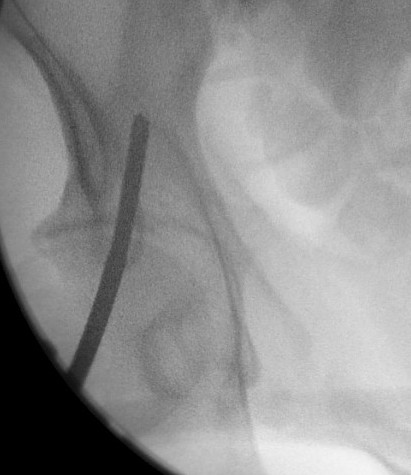

Entry point of steinmann pins

- intersection of 2 lines

- line parallel with femur / line back from ASIS